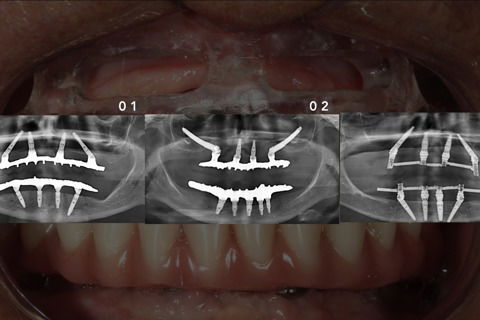

Técnica All-on-4: Caso 1 e 3 implantes inclinados, Caso 2: Associado ao implante zigomático

Foto 11 Técnica All-on-4: Caso 1 e 3 implantes inclinados, Caso 2: Associado ao implante zigomático